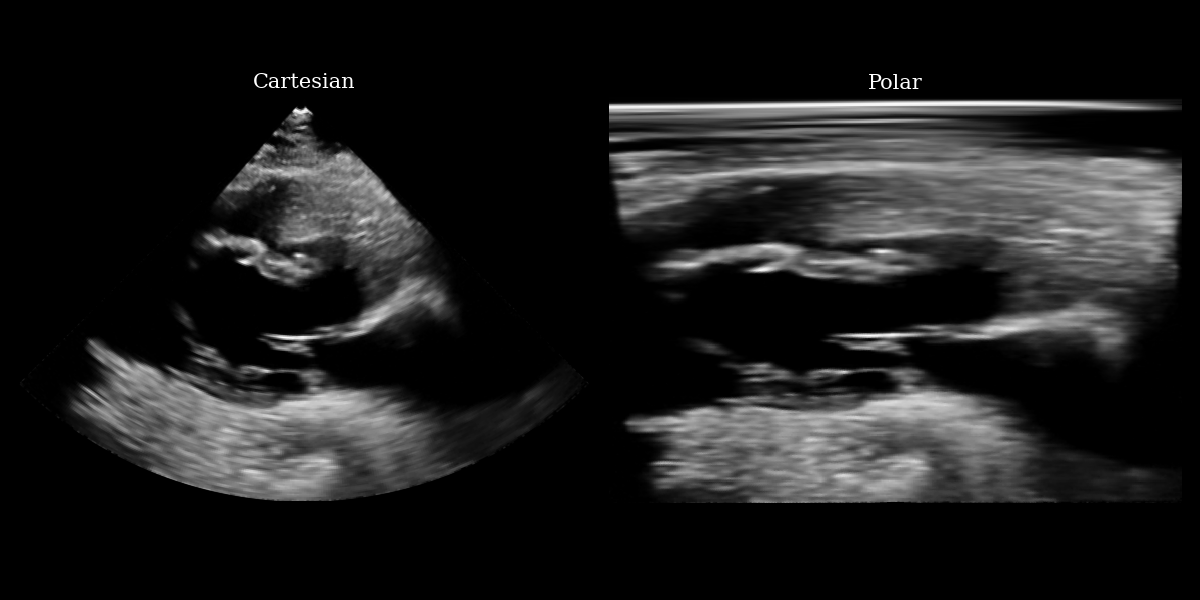

fig, (ax1, ax2) = plt.subplots(1, 2, figsize=(12, 6))

ax1.imshow(img_np, cmap="gray")

ax1.set_title("Cartesian", fontsize=15)

ax1.axis("off")

ax2.imshow(img_polar_np, cmap="gray")

ax2.set_title("Polar", fontsize=15)

ax2.axis("off")

plt.tight_layout()

plt.savefig("cartesian_polar.png")

plt.close()

Cartesian Polar input